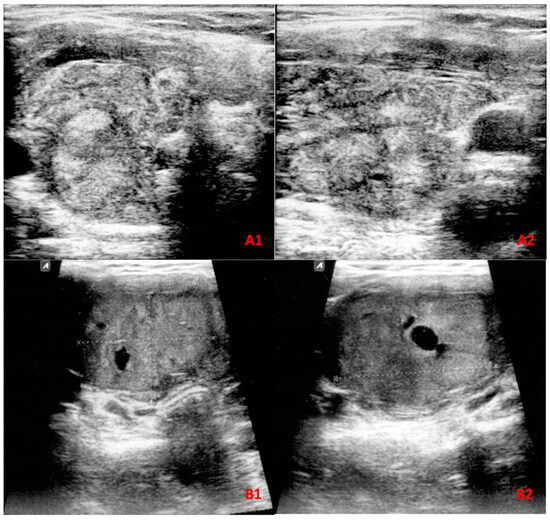

This prospective study was carried out on all patients with thyroid nodule(s) who underwent FNA biopsy from January 2018 to January 2022 at the Endocrinology Department of Imam Reza Hospital, affiliated with Mashhad University of Medical Sciences, Mashhad, Iran. During the study period, 813 patients with 869 aspirated nodules were referred to our department. These patients were followed for 6 months, and post-surgery histopathology results were recorded when available. Among all nodules, 283 nodules were excluded due to inconclusive final diagnosis, and 15 nodules were excluded as they were not classifiable according to the ATA guideline; however, they were assessed with ACR TI-RADS and followed to obtain a final diagnosis when available (Figure 1(A1,A2)). Of excluded nodules, 113 were classified as Bethesda grades III, IV, and V, while 170 nodules had nondiagnostic or unsatisfactory FNA findings (Bethesda grade I). As these patients either refused to undergo repeated FNA cytopathology examination or had a second inconclusive FNA cytopathology result and declined surgery within the 6-month follow-up period, a final diagnosis could not be obtained, and these nodules were thus excluded from further analysis. Eventually, 571 thyroid nodules were included of which 95 were diagnosed using histopathology results and 476 were diagnosed based on FNA cytology reports (Figure 2). Among nodules diagnosed as malignant, 61 out of 65 lesions had a confirmed post-surgical histopathologic result. Malignancy was diagnosed on the basis of Bethesda grade VI in four patients as three were lost to follow-up and the other refused surgery.

4.2. ACR TI-RADS and ATA Guidelines Diagnostic Performance

The optimal cut-off values for all nodules and nodules larger than 4 cm were TR4 and TR5 for ACR-TIRADS, as well as intermediate and high suspicion for the ATA guideline (Table 3). ACR TI-RADS had an accuracy of 78.4% at these cut-off points across all nodules, regardless of size, whereas the ATA guideline had an accuracy of 80.9%. There was no statistically significant difference between these two guidelines’ accuracy (p = 0.203). Figure 1(B1,B2) illustrate a malignant nodule that was missed by both ACR-TI-RADS and the ATA guideline based on their optimal cut-off points.

Figure 1. Transverse (A1) and longitudinal (A2) US views of a solid, isoechoic nodule with a smooth margin, largest diameter of 1.64 cm, and a taller-than-wide shape in a 41-year-old female. This nodule is classified as TR4 despite not being classifiable according to ATA guidelines. The nodule was finally diagnosed as FTC. Transverse (B1) and longitudinal (B2) US views of a nodule from a 31-year-old female patient illustrate a solid, isoechoic nodule with a smooth margin, largest diameter of 4.06 cm, and a wider-than-tall shape. This nodule is classified as TR3 and low suspicion by ACR TI-RADS and ATA guidelines, respectively. FNA cytology reported grade V Bethesda, and upon follow-up, the lesion was diagnosed as PTC by histopathology.